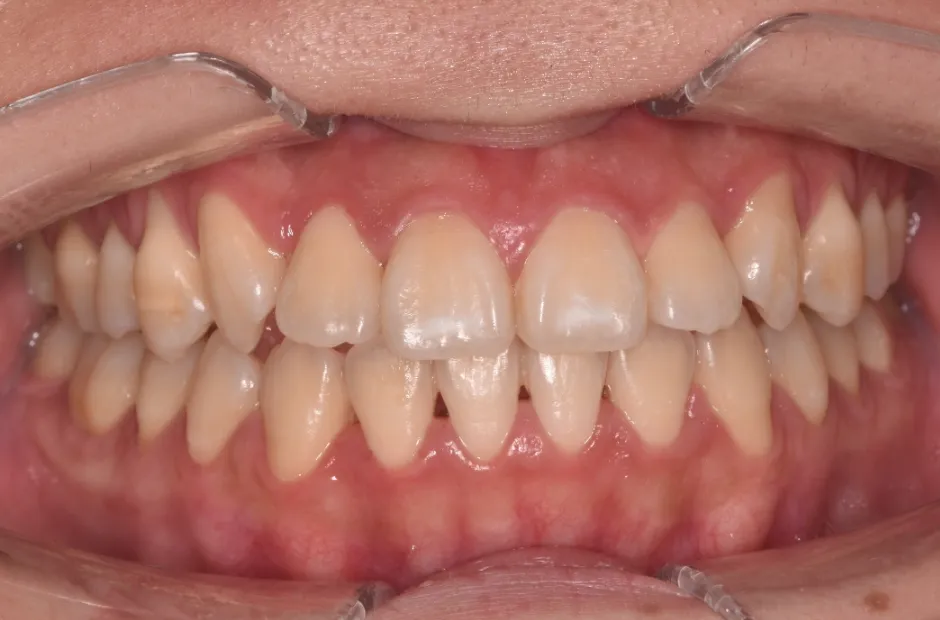

叢生

| 診断名・主訴 | 叢生 |

|---|---|

| 年齢・性別 | 43歳・女性 |

| 治療期間・回数 | 2年7か月 27回 |

| 治療に用いた主な装置 | 舌側矯正 |

| 抜歯部位 | 両顎4,4 |

| 治療費 | 100万円(税抜) |

| リスク・副作用 | 装置による違和感・疼痛・歯肉退縮・歯根吸収・虫歯のリスクなど |